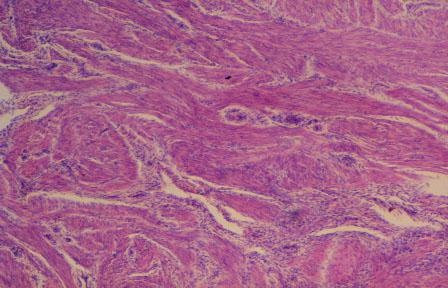

XI-53 (4) Slide 103, Uterus (H&E). Medium power view of myometrium. Observe complex intermingling layers of smooth muscle cells.